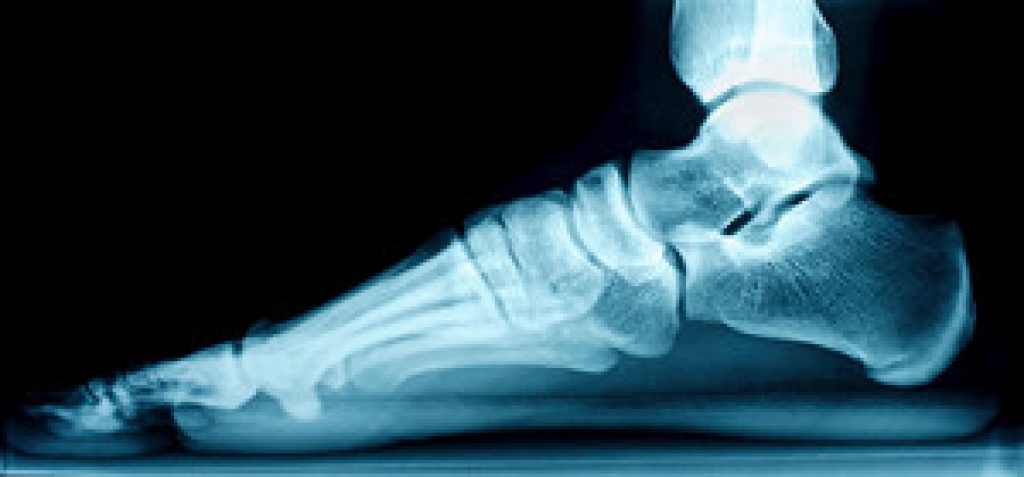

A broken ankle is experienced when a person fractures their tibia or fibula in the lower leg and ankle area. Both of these bones are attached at the bottom of the leg and combine to form what we know to be our ankle.

When a physician is referring to a break of the ankle, he or she is usually referring to a break in the area where the tibia and fibula are joined to create our ankle joint. Ankles are more prone to fractures because the ankle is an area that suffers a lot of pressure and stress. There are some obvious signs when a person experiences a fractured ankle, and the following symptoms may be present.